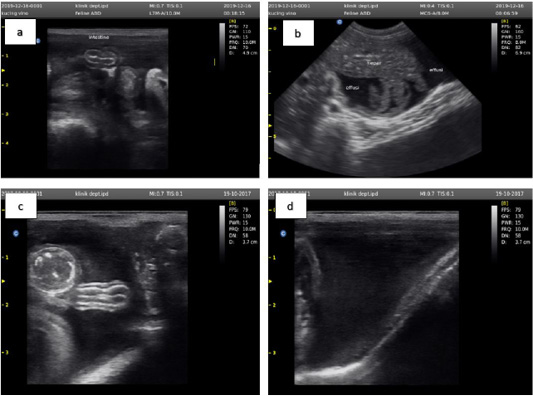

Figure 2

Ultrasound examination results showed an accumulation of anechoic fluid between the small intestine (a), liver (b), large intestine (c), and outside the bladder wall (d).